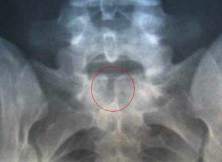

Gai cột sống có cần phẫu thuật? (26/03/2011)

Tôi bị đau vùng thắt lưng đã hơn 3 tháng...